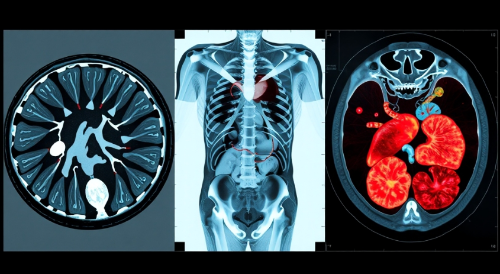

CT 촬영은 X선을 사용해 몸 안을 단면으로 촬영하는 검사예요. 뼈나 장기 상태를 확인하는 데 효과적이며, MRI와 달리 자기장을 사용하지 않아요.

CT 촬영은 골절, 출혈, 암 진단, 감염 확인 등 다양한 상황에서 필요해요. 특히 응급 상황에서 빠르고 정확한 진단에 필수적이죠. 예를 들어, 교통사고 환자의 장기 손상이나 뇌출혈 위치를 빠르게 파악할 수 있어요.

CT는 X선을 이용해 신체 단면을 촬영하며, 빠르고 정확하게 뼈나 장기 상태를 확인할 수 있어요. 하지만 방사선 피폭량이 다른 검사에 비해 높은 편이죠.